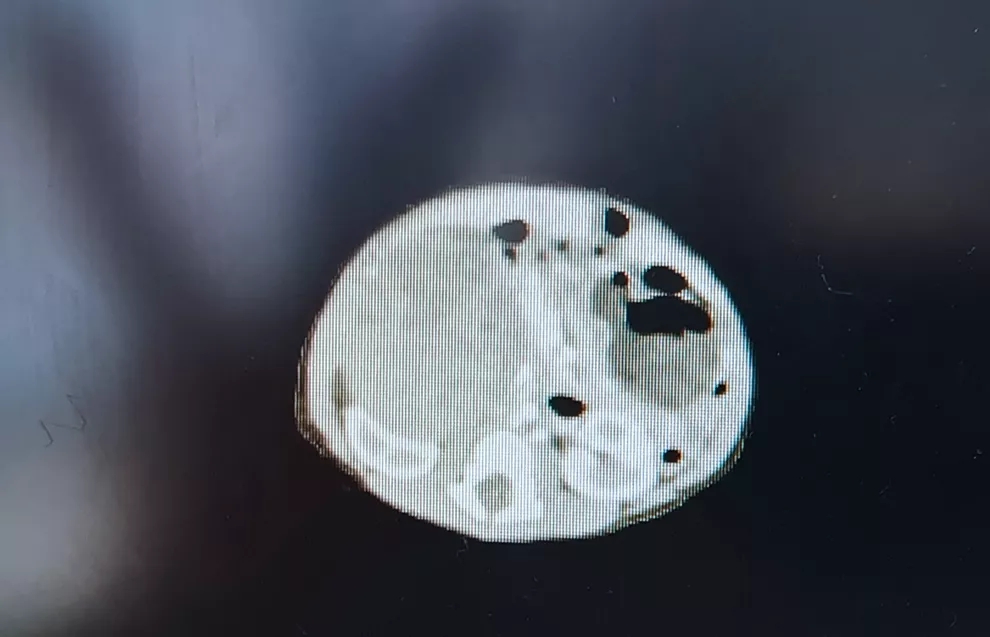

▲CT影像:5日大患儿体内的肿瘤

据悉,患儿母亲产前定期产检,孕33周产检并未发现胎儿腹腔占位,在孕35周产前发现胎儿腹腔占位,且发现时肿瘤即为48*36mm大小。短短的两周时间,患儿身体内的肿瘤增长近50mm,生长迅速,且来源不明,较为罕见。患儿出生后在外院进行B超检查,结果提示为右肾中上部实质性占位病变,当时肿瘤大小约为52*40mm。患儿家长经深思熟虑后,选择到我院小儿外科就诊。

患儿入院后,医护团队立即为其进行CT和3D成像检查,小儿外科主任邓洪强结合各项检查结果,分析患儿的腹腔占位来源于肾上腺可能性较大,各项指标更倾向于神经母细胞瘤的诊断。如肿瘤继续进展,预后极可能不佳,医护团队考虑为其实施外科手术。由于患儿出生仅5日,存在肿瘤基础疾病,治疗耐受差,肿瘤与腹腔内的重要血管关系密切,手术风险极高。主刀潘云副主任医师在征得家属同意后,为该患儿实施手术。

12月6日,患儿在全麻下行腹膜后肿瘤切除术,术中见肿瘤来源于右侧肾上腺,大小为8*8*6cm。肿瘤不仅占据很大的空间,且与右侧肾脏,肝门静脉,肝动脉粘连紧密,如稍有不慎,即可能出现血管破裂大出血的情况。潘云细心分离结扎肿瘤血管,减少术中出血。最终,在手术室麻醉科配合下,肿瘤完整切除。术后病理提示为神经母细胞瘤。肿瘤切除后,患儿在小儿外科全体医护人员的精心照顾下,病情逐渐好转,现已康复出院。